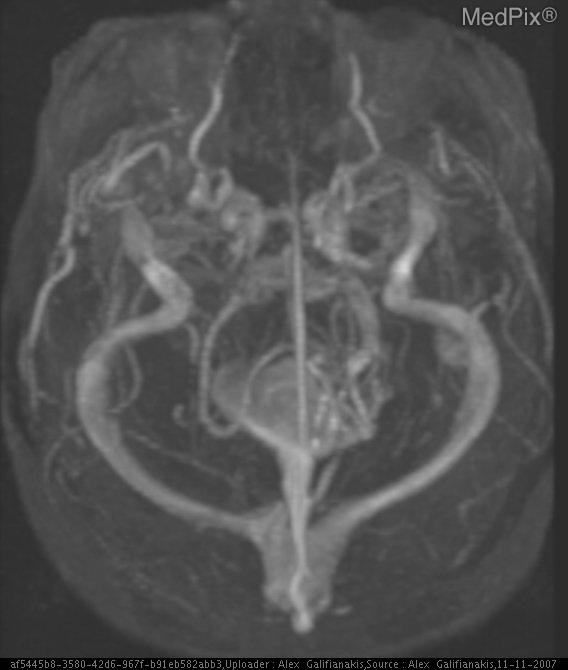

лизация мальформации

Эмболизация мальформации 113 фотографий